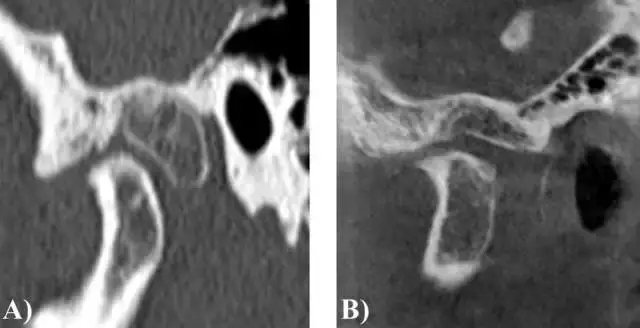

圖 1. 病例 1 的 CT 圖像 (A)術前 (B)術后